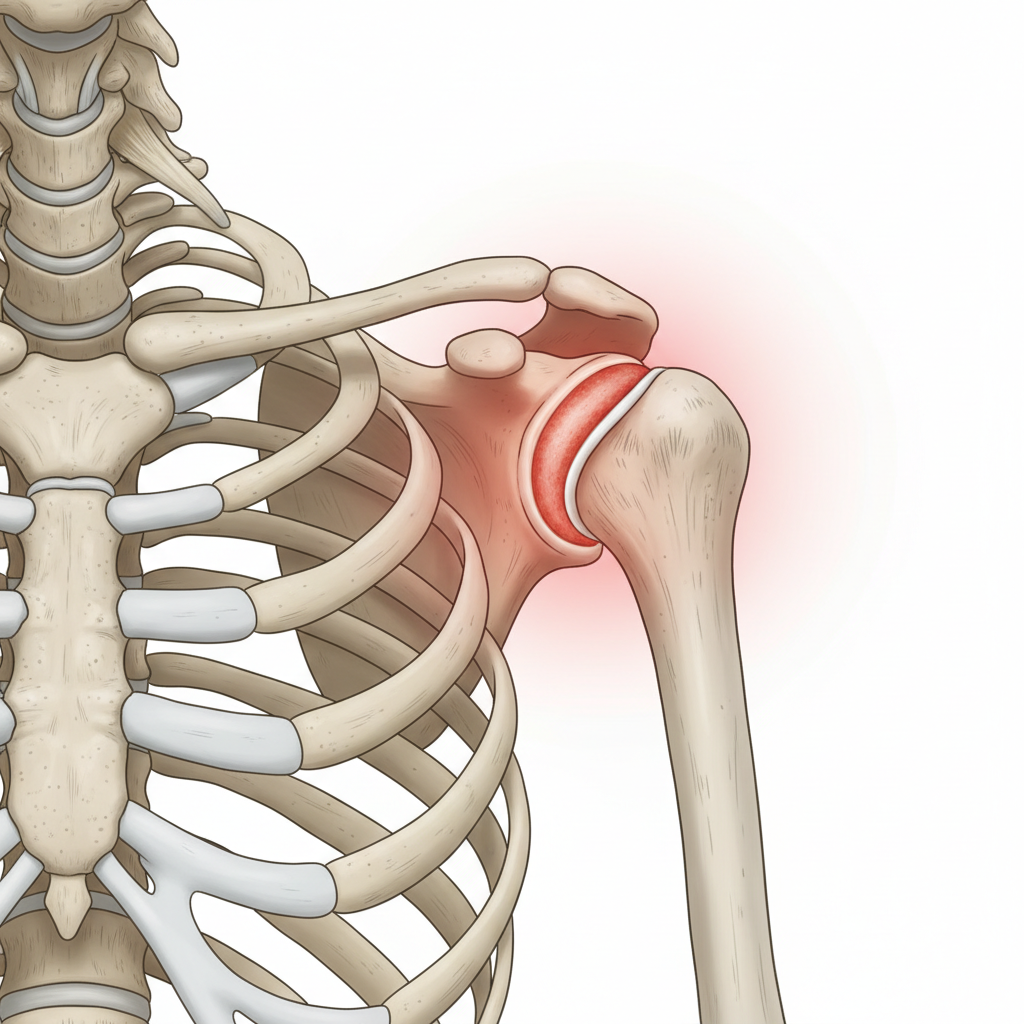

ICF: Health Condition

• Frozen Shoulder (Adhesive Capsulitis)<br>• Post-traumatic onset after a fall<br>• Right shoulder affected<br>• X-ray: no abnormalities (fractures ruled out)

Clinical Reasoning: Hypothesis

• Post-traumatic shoulder condition<br>• Pain combined with global stiffness<br>• Loss of active and passive ROM in multiple planes<br>• Presentation consistent with Frozen Shoulder

Possible Diagnosis

<strong>Frozen Shoulder (Adhesive Capsulitis)</strong><br><br>• Structural damage (fracture/tear) ruled out by imaging and assessment.<br>• Diagnosis is clinical, based on global restriction and history.